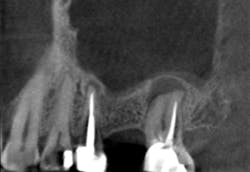

Although unpredictable, a greater amount of alveolar ridge loss following extraction usually occurs in the horizontal dimension and affects the buccal bone of the ridge.3 In fact, 50% of alveolar bone dimension can be lost after tooth extraction, with losses reported of up to 6–7 mm (figure 1). Two-thirds of this loss of bone volume can occur within the first three months of tooth extraction.4

Because of this alveolar resorptive pattern after tooth extraction, bone grafting the extraction socket after tooth extraction procedures has become a solution that attempts to limit the amount of hard- and soft-tissue loss. There are many systematic reviews in the literature that compare the results of residual ridge dimension following tooth extraction after the use of a bone graft (with or without a membrane) versus extraction alone without grafting.7